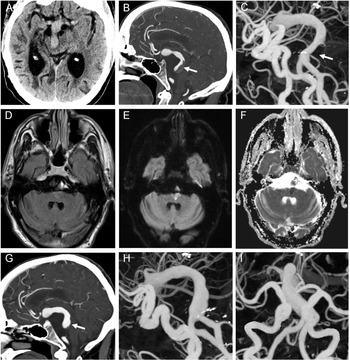

Figure 1: Axial noncontrast CT head demonstrating the presence of a dolichoectatic basilar artery with mass effect on the midbrain (A). With contrast administration, the sagittal CT angiography demonstrated a nonocclusive thrombus in the dolichoectatic basilar artery denoted by the arrow (B). Three-dimensional (3D) digital angiography reconstruction further highlighted the extent of intracranial arterial dolichoectasia in both the anterior and posterior circulation with the associated nonocclusive thrombus in the basilar artery denoted by the arrow (C). MRI axial T2 FLAIR brain imaging demonstrated a subtle hyperintensity in the left paramedian pontine region (D), with associated increased signal on diffusion-weighted imaging (E) and decreased signal on apparent diffusion coefficient imaging (F) consistent with an acute ischemic infarct. Repeat CT angiography showed an interval decrease in the size of the nonocclusive thrombus in the dolichoectatic basilar artery denoted by the arrow (G). There is also interval improvement in the caliber of the basilar artery on the 3D digital angiography reconstructions (H, I) in the setting of ongoing diffuse intracranial arterial dolichoectasia.

He was started on a heparin infusion given that the extensive clot burden in the dolichoectatic basilar artery remained relatively unchanged post-tPA. A subsequent MRI ruled out any acute ischemia and he was transitioned to warfarin. Eleven days after his initial presentation, while therapeutic on warfarin, he developed recurrent right-sided weakness and anarthria with an NIHSS of 10. Repeat CT angiography showed no interval change in thrombus size or intracranial hemorrhage, but his MRI showed a new left paramedian pontine infarct (Figure 1D-F). Given his new ischemic stroke, low dose aspirin was added to his anticoagulation. His 3-month follow-up imaging showed decreased size of the thrombus in the dolichoectatic basilar artery (Figure 1G-I) while on warfarin and low-dose aspirin.